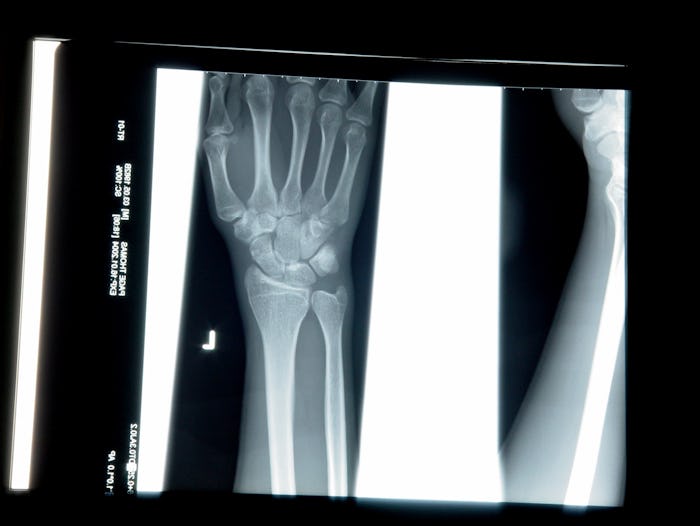

Well, don’t cancel that dentist appointment yet (I know, sorry about that.) It turns out all X-rays are safe while nursing and have no effect on your breast milk, according to Breastfeeding Support. Now, that’s not to say your milk won’t be affected. As Pediatrician Natasha Burgert noted on BabyCenter X-ray radiation can kill off a few living cells in your breast milk, but your baby won’t be exposed to the rays. She also noted that some screenings may require more caution. Burgert wrote that if you undergo an X-ray that requires the injection of radioactive isotopes, such as a marrow or bone scan, you may have to wait to resume breastfeeding.